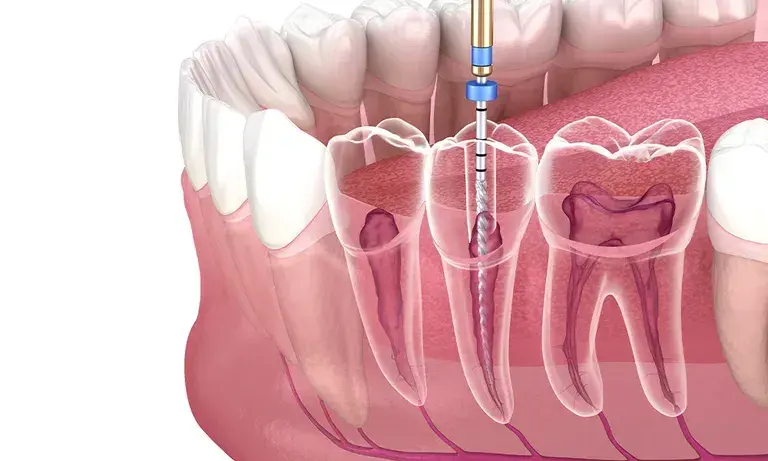

Root Canal Procedure

Our comprehensive root canal procedure involves several precise steps to ensure complete treatment and long-term success:

- Thorough examination and digital X-rays to assess the tooth condition

- Local anesthesia for complete comfort during the procedure

- Creation of small access opening to reach the root canals

- Removal of infected or damaged pulp tissue

- Cleaning, shaping, and disinfecting the root canal system

- Filling and sealing the canals with biocompatible material

- Placement of temporary or permanent filling

- Final restoration with crown for long-term protection

Specialist endodontist performing precise root canal treatment